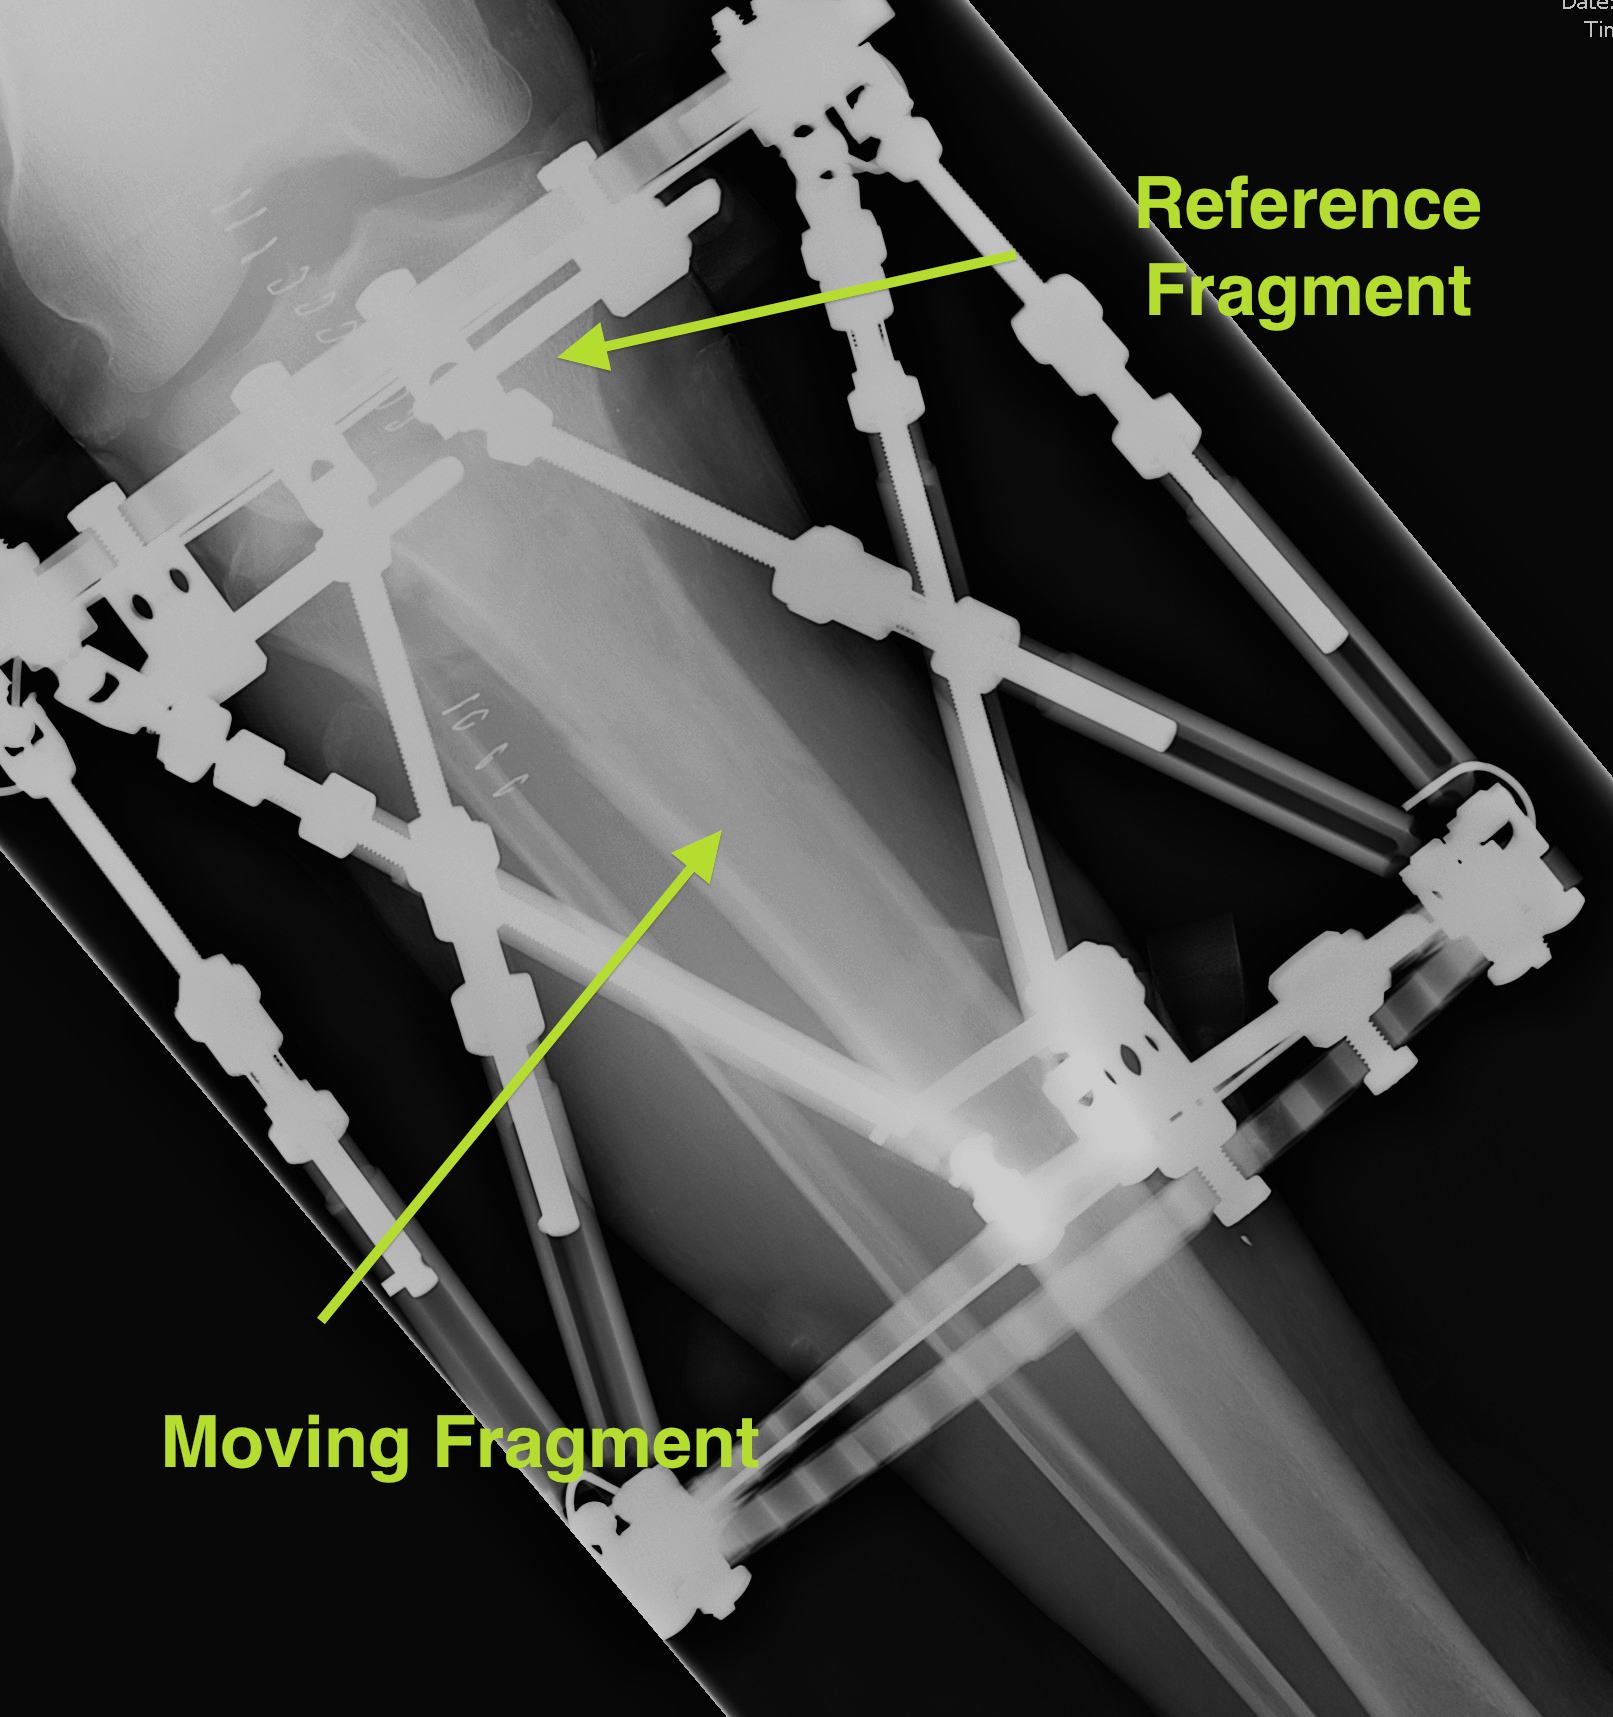

Set reference fragment

Proximal tibia

- usually the proximal fragment is reference fragment

- distal fragment is moving fragment

Opposite for Distal Tibial Fractures